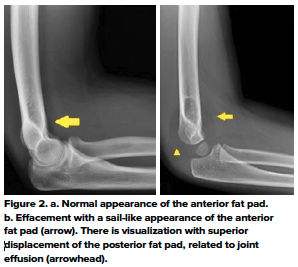

The elbow fat pads are situated external to the joint capsule. On a true lateral radiograph, the normal anterior fat pad is seen as a radiolucent line parallel to the anterior humeral cortex; and the posterior fat pad is invisible.

Distention of a structurally intact joint causes displacement of the fat pads - the posterior fat pad moves posteriorly and superiorly and becomes visible; the anterior fat pad becomes more sail-like.4 (Fig 2)

On the lateral x-ray of the elbow, a joint effusion can be inferred when there is displacement of the anterior fat-pad or presence of the posterior fat pad. An elbow joint effusion without a visible fracture seen on radiographs can suggest an occult fracture and should prompt further evaluation.

A study by Major et al.5 showed that a joint effusion without visible fracture seen on conventional radiographs is often associated with an occult fracture and bone marrow edema on MRI. The study found that 57% of imaging where the only finding was joint effusion had a fracture and 100% had bone marrow edema on MRI. In cases where an occult fracture is suspected, follow-up radiographs in 7-10 days can be obtained to evaluate for the presence or absence of sclerosis or periosteal new bone formation as indicators of healing. For suspected occult fractures, standard of care remains posterior elbow splinting with follow-up radiographs at 7-10 days.